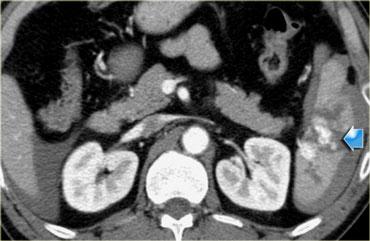

Bên trái là một bệnh nhân khác với chấn thương xuyên thấu do vết đâm dao ở hông.

CT cho thấy rõ ràng rằng tổn thương giới hạn trong khoang sau phúc mạc với khối máu tụ nhỏ quanh thận.

Không có dấu hiệu vi phạm phúc mạc và trên hình ảnh pha muộn (không hiển thị) không có hiện tượng thoát thuốc cản quang từ hệ thống thu thập nước tiểu.

Bệnh nhân này sẽ được điều trị bảo tồn không phẫu thuật